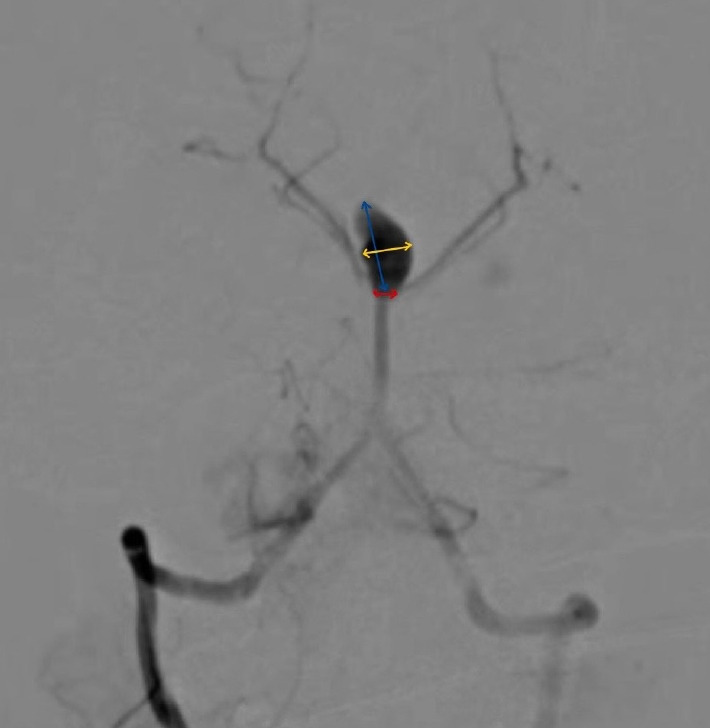

Fahr病是一种罕见的疾病,其特征是认知、精神和运动功能逐渐下降,与基底节区特发性钙化有关,通常以常染色体显性方式遗传。急性表现通常为癫痫发作;然而,我们提出了一个病例的急性表现,其中恶化的原因是动脉瘤性蛛网膜下腔出血。Fahr病与颅内动脉瘤之间的关联极为罕见,迄今为止文献记载的病例只有5例。本报告是第六次这样的案例。此外,所有先前报道的动脉瘤都局限于前循环;因此,这是第一例以后循环动脉瘤为表现的Fahr病。本病例以严重头痛主诉送急诊。头部CT显示双侧基底节区钙化及蛛网膜下腔出血。数字减影血管造影(DSA)显示颅底尖端动脉瘤。动脉瘤采用Neqstent辅助盘绕术治疗。术中动脉瘤出血发生在置入第一圈后。肝素被逆转,血压下降,动脉瘤被进一步的线圈包裹,直到出血停止。采用脑室外引流术治疗蛛网膜下腔出血和脑室内出血。Fahr病的确切机制尚不完全清楚,但据信它在由血管中的矿物质沉积引起的动脉瘤的发展中起作用。对于出现不明原因的反复发作的意识丧失的患者,即使他们已经诊断为Fahr病,也应进行脑计算机断层血管造影(CTA)以排除动脉瘤,以防止将这些发作错误地归因于癫痫。此外,对于伴有Fahr病或血管炎的动脉瘤,术前应进行血管壁磁共振成像(MRI)检查,以改善治疗计划。

Fahr's disease is an uncommon condition characterized by a gradual decline in cognitive, psychiatric, and motor functions, linked to idiopathic calcification in the basal ganglia, typically inherited in an autosomal dominant fashion. Acute presentation is most often as a seizure disorder; however, we present a case of an acute presentation in which the cause of the deterioration was an aneurysmal subarachnoid haemorrhage. The association between Fahr's disease and intracranial aneurysms is exceedingly rare, with only five cases documented in the literature to date. This report represents the sixth such case. Furthermore, all previously reported aneurysms were confined to the anterior circulation; thus, this is the first documented instance of Fahr's disease presenting with an aneurysm in the posterior circulation. The case here presented to the emergency service with the complaint of severe headache. Computed tomography (CT) of the head showed bilateral basal ganglia calcification and subarachnoid haemorrhage. Digital subtraction angiography (DSA) revealed a basilar tip aneurysm. The aneurysm was treated with Neqstent assisted coiling via jailing technique. Intraoperative aneurysmal haemorrhage occurred just after inserting the first coil. Heparin was reversed, blood pressure decreased and aneurysm was packed with further coils till the bleeding stopped. External ventricular drainage was performed to address subarachnoid hemorrhage (SAH) and intraventricular hemorrhage. The exact mechanisms underlying Fahr's disease are not fully understood, but it is believed to play a role in the development of aneurysms due to mineral deposits in blood vessels. For patients experiencing unexplained recurrent episodes of loss of consciousness, brain computed tomography angiography (CTA) should be performed to rule out an aneurysm, even if they have a known diagnosis of Fahr's disease, to prevent misattributing these episodes to epilepsy. Additionally, vessel wall magnetic resonance imaging (MRI) should be conducted preoperatively in cases of aneurysms linked to Fahr's disease or vasculitis to improve management planning.